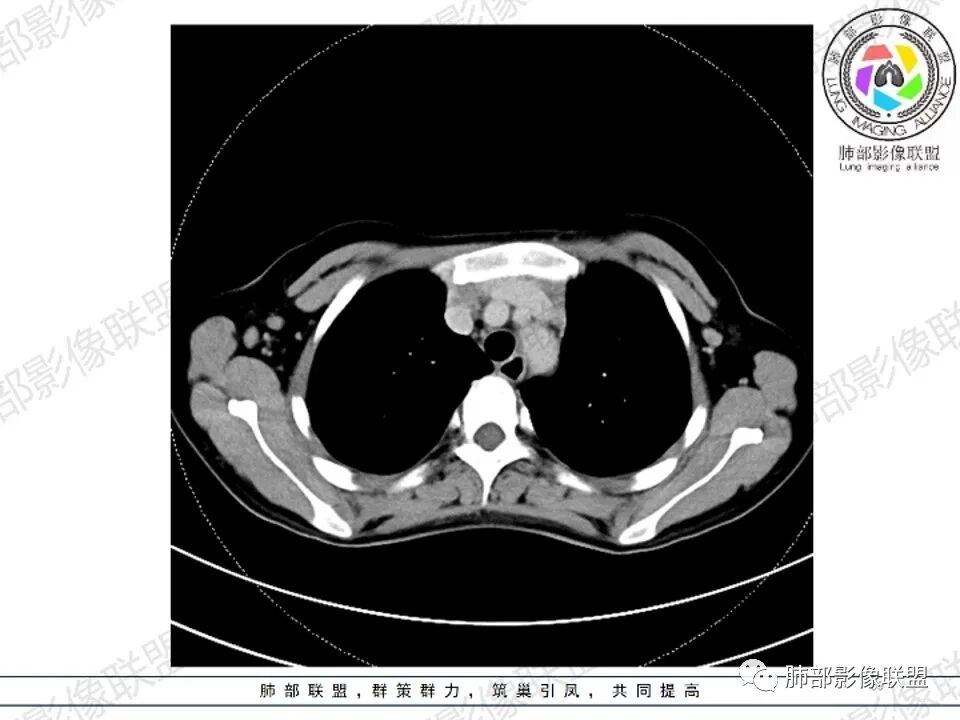

2.影像显示前纵隔不规则块状影,依势贴附心脏大血管旁,密度不均,边界不甚清楚,有结节融合感。

3.病灶轻度不均匀强化,可见血管穿行,散在液性低密度区。

双肺门未见肿大淋巴结。

4.双侧腋窝区见增大淋巴结,边界清楚。